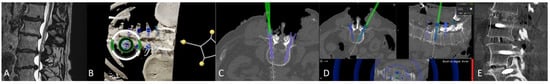

• Preoperative imaging and screw planning. In addition to magnetic resonance imaging (MRI) of the spinal region to be examined and instrumented, all patients received preoperative three-dimensional (3D) CT imaging of the part of the spine that was to be stabilized. The MRI and CT data were exported to the BrainLab navigation software (https://www.brainlab.com/surgery-products/overview-spinal-trauma-products/spinal-navigation/, accessed date 20 June 2025) and fused either rigidly or elastically. The navigation software includes a screw planning application that was used to plan the radius, length, and trajectory of the PS prior to surgery. The software enables automatic identification of the vertebra, followed by automatic screw planning for PSs in the selected vertebra. The proposed preplanned screws were then manually corrected according to the surgeon’s preference. For this step, it was crucial to have an artifact-free, high-resolution 3D CT of the spine, i.e., the area intended for instrumentation. (Figure 1 and Figure 2) [4].

Figure 1. Preoperative (A) anterior–posterior (AP) and (B) sagittal reconstruction of bone anatomy according to preoperative CT with automatic identification of vertebras. (C) Screw recommendations in selected vertebrae for stabilization of L4-S1.

Figure 2. Screw planning includes the entry point, trajectory, diameter, and length of the screw. The proposed screw plan can be modified manually according to the surgeon’s preference.

Figure 9. Same patient as in Figure 1, Figure 2 and Figure 7. (A) iCT scan with AI-assisted vertebra recognition. (B) Screw trajectory in the preoperative CT. (C) iCT scan after fusion with preoperative CT shows the screw trajectories, with the option of correcting the screw planning according to the iCT scan.